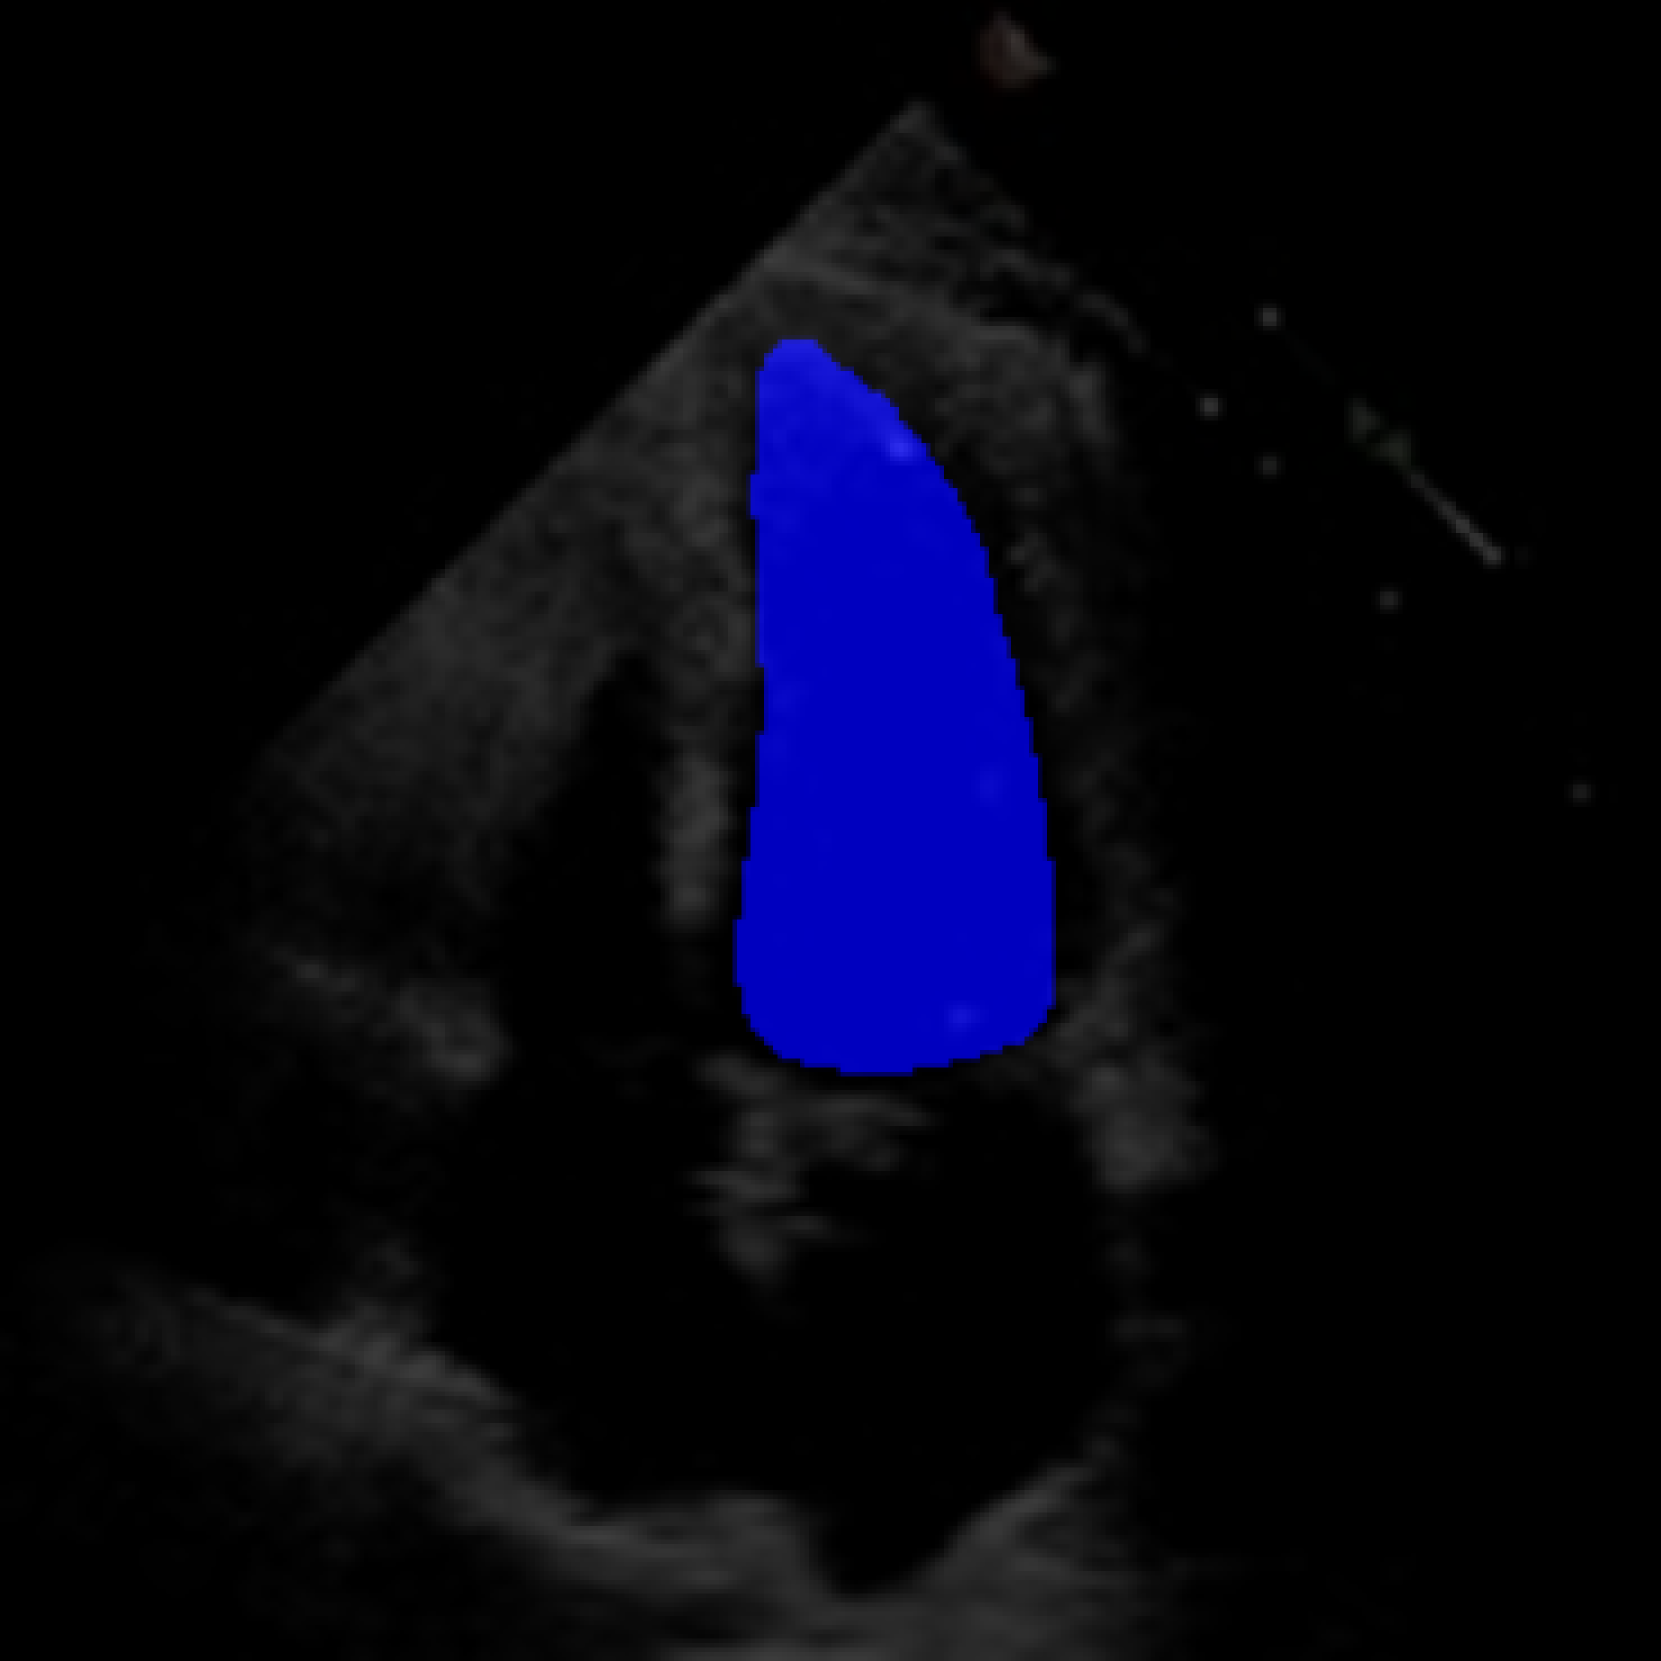

The 112x112 input is first resized to 299x299 as required by the Xception model. The Beat Extractor is then used to feed only whole beats to the LVEF estimation pipeline. A modified DeepLabV3+ model segments the left ventricle for every frame of the echocardiogram video (Figure LABEL:fig:segmentation). The area is measured, and a peak detector is then used to find the maximum (diastole) and minimum area (systole). The frame numbers corresponding to these extrema are recorded, and the video is clipped into smaller videos that go from diastole to systole. These smaller videos are independently fed to the Xception based feature extractor.

The ConFormer model demonstrated high performance in the estimation of Left Ventricular Ejection Fraction (LVEF) from echocardiogram videos (Figure 2). The model achieved a mean absolute error of 6.57 in LVEF prediction, indicating a high level of accuracy in its estimations (Table I). Notably, ConFormer outperforms the full video assessment of LVEF by EchoNet-Dynamic, a significant achievement given the model’s efficiency. With just 5.82 million parameters, ConFormer is significantly more efficient than existing models, making it a practical tool for real-world applications.